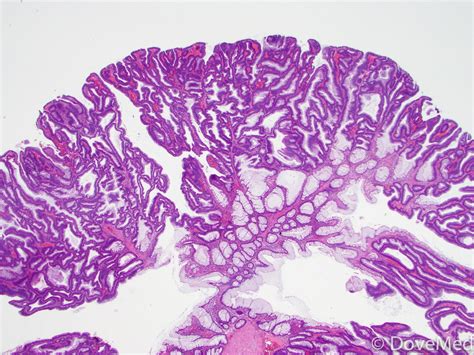

A tubular adenoma is a type of polyp that forms on the inner lining of the colon. These polyps are composed of glandular tissue and are characterized by their tubular shape. Tubular adenomas are the most common type of adenomatous polyps, which are known to have the potential to become malignant if left untreated. Early detection and removal of these polyps are essential for preventing the development of colorectal cancer.